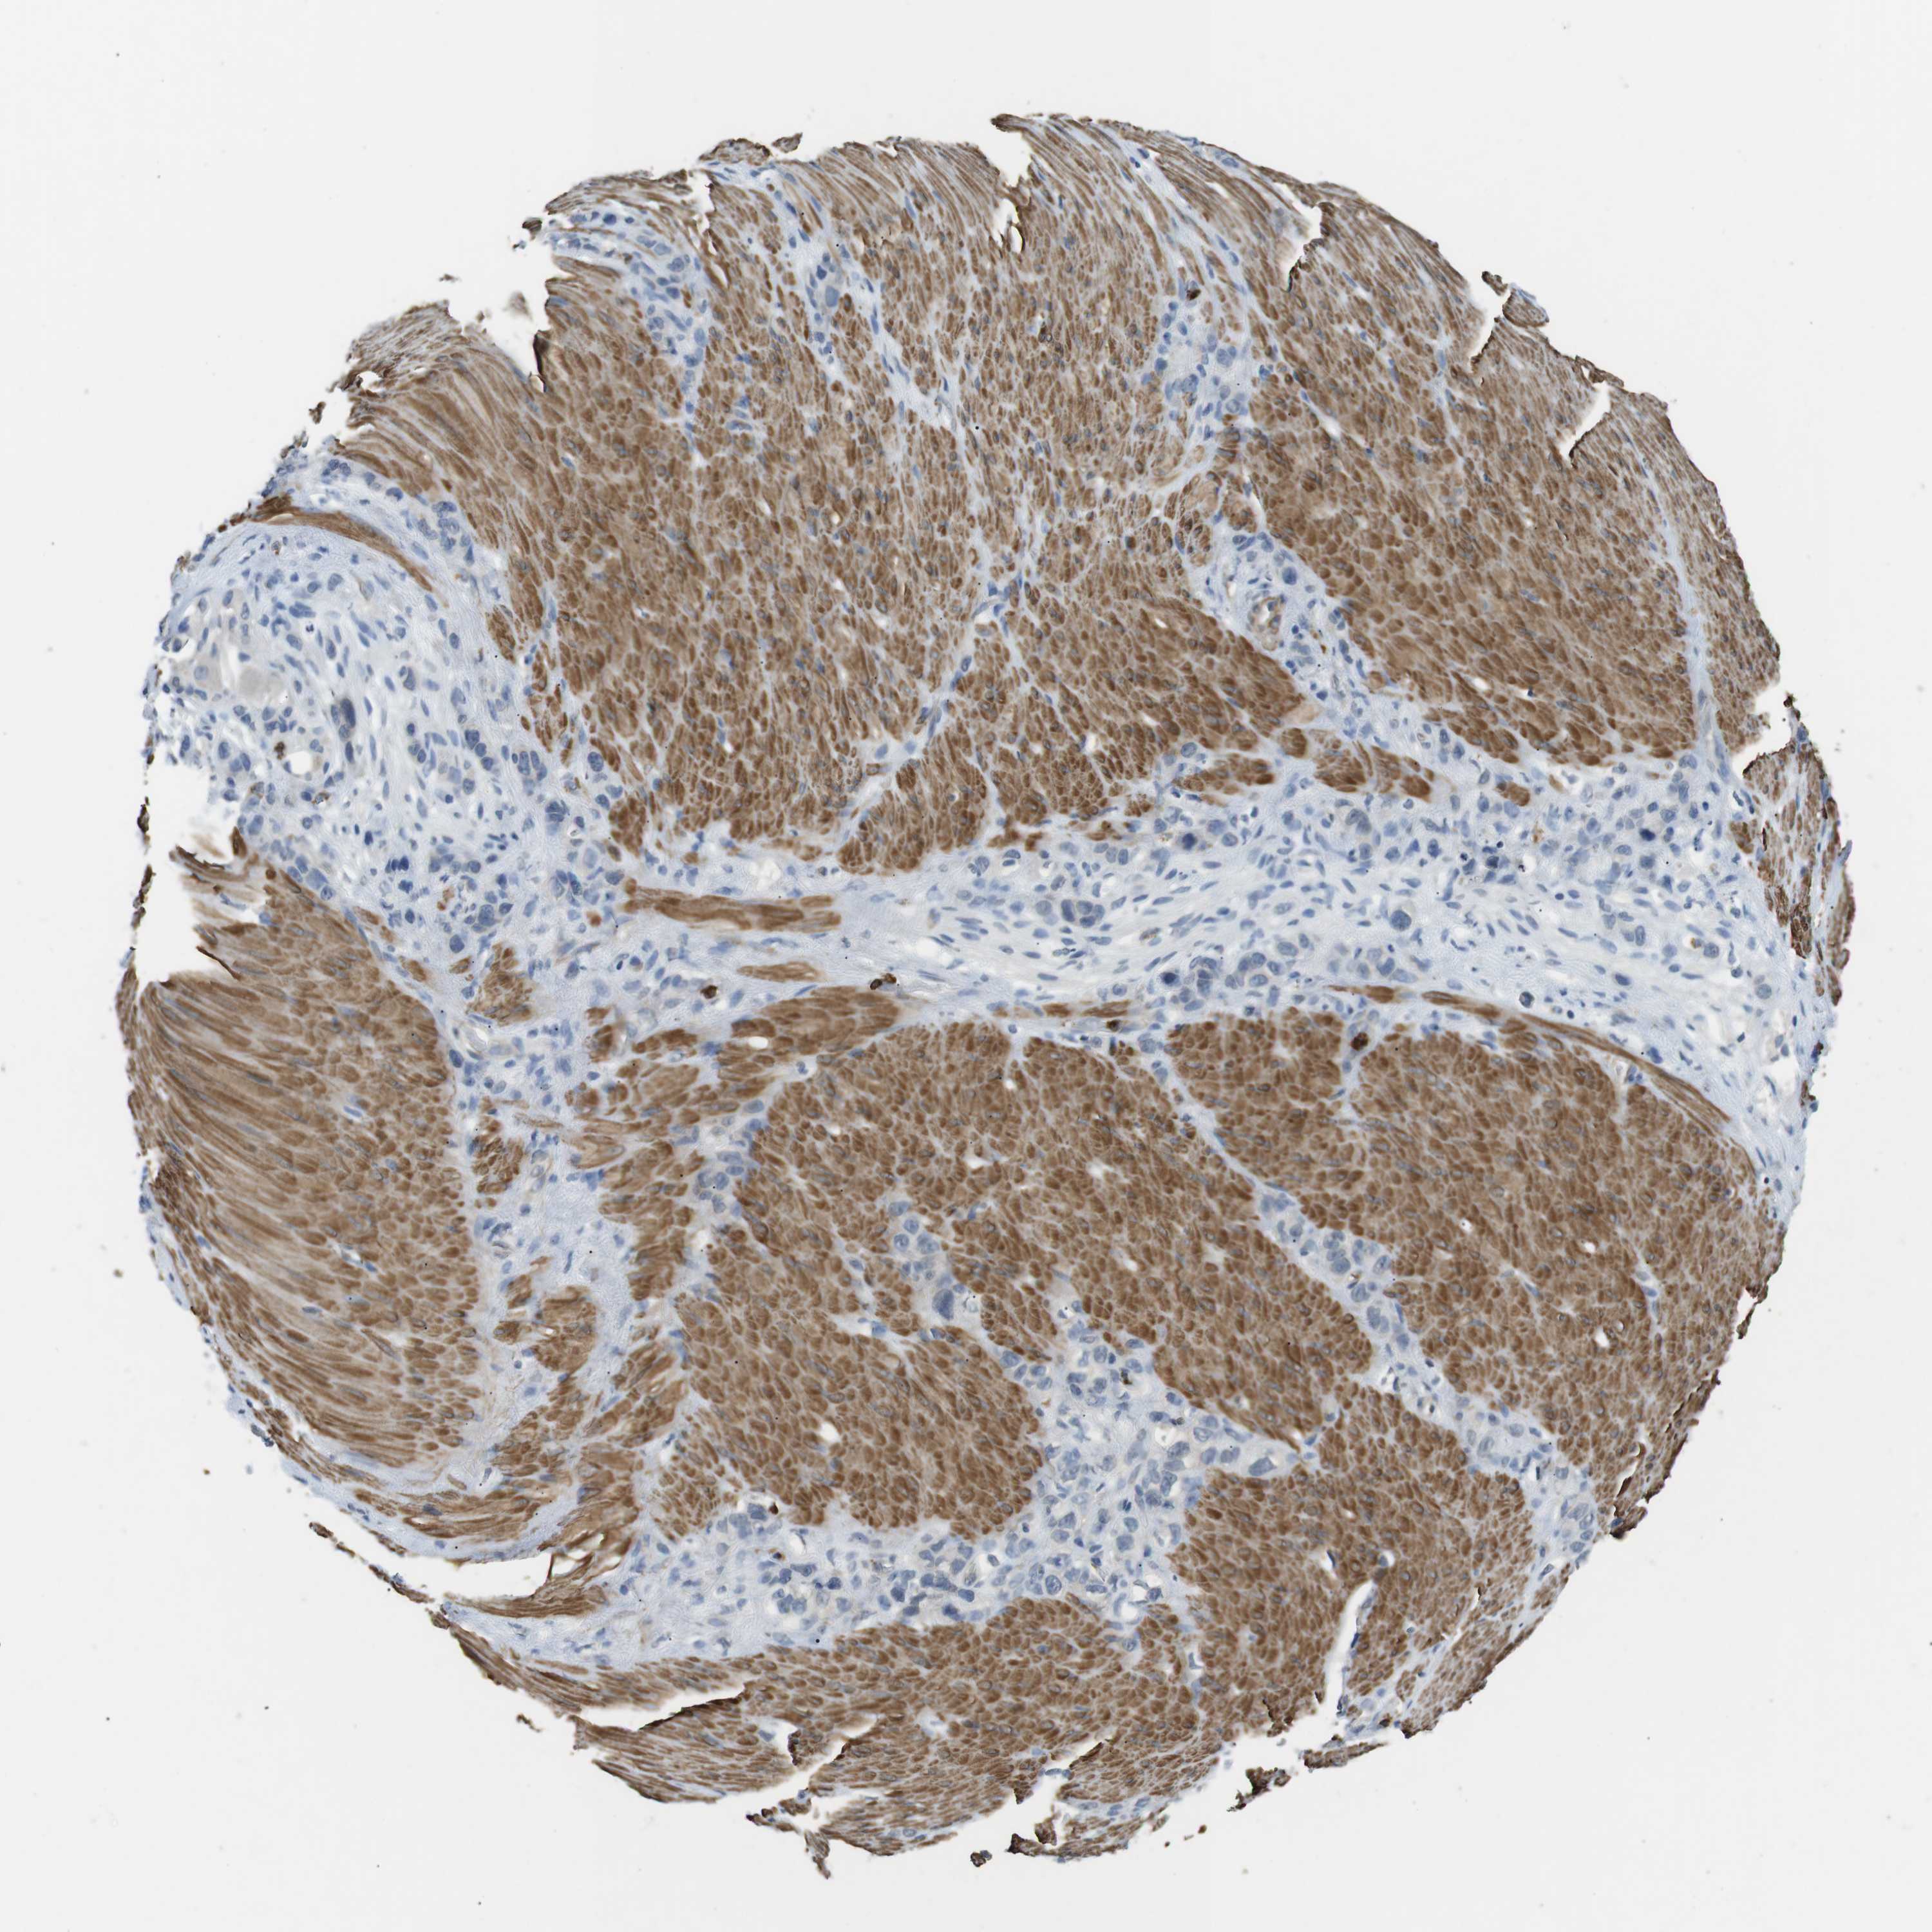

STOMACH CANCER - Protein expressioni

A mouse-over function shows sample information and annotation data. Click on an image to view it in a full screen mode. Samples can be filtered based on level of antibody staining by selecting one or several of the following categories: high, medium, low and not detected. The assay and annotation is described here.

Antibody stainingi

Antibody staining in the annotated cell types in the current human tissue is reported as not detected, low, medium, or high, based on conventional immunohistochemistry profiling in selected tissues. This score is based on the combination of the staining intensity and fraction of stained cells.

Each image is clickable and will lead to virtual microscopy that enables deeper exploration of all samples and also displays staining intensity scores, fraction scores and subcellular localization as well as patient and tissue information for each sample.

Antibody HPA015624

Staining

High

Medium

Low

Not detected

Intensity

Strong

Moderate

Weak

Negative

Quantity

>75%

75%-25%

<25%

None

Location

Nuclear

Cytoplasmic/membranous

Cytoplasmic/membranous,nuclear

Adenocarcinoma, NOS

Adenocarcinoma, High grade